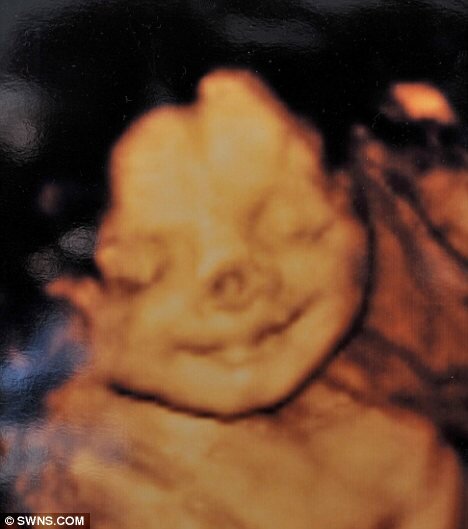

2008-ci ilin sentyabr ayında Lloyd ailəsində Konni adlı qız uşağı dünyaya gəlib. Onun burnundakı qırmızı xal körpəni digərlərindən fərqləndirib. Bu ləkə ana bətnində 32 həftəlik embrionun USM müayinəsi zamanı da görünüb.

Belə ki, Konniyə gemangioma diaqnozu qoyulub. Bir neçə ilə ləkənin sovrulub keçəcəyi deyilsə də, 3 yaşına çatdıqda qızın xalı, müalicələrə baxmayaraq, böyüyərək bütün burnunu örtmüş olub. Bu, onun valideynləri Zara və Tomu narahat etməyə başlayıb.